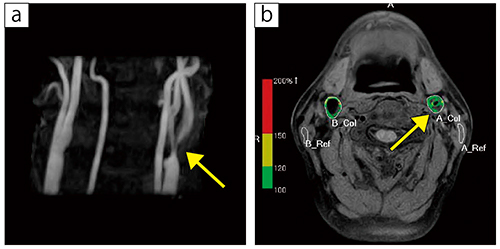

■症例2:左内頸動脈プラーク

60歳代,男性。無症候性頸動脈狭窄(高度狭窄)の症例。左頸部にブルイ(頸動脈血管雑音)聴取され,超音波検査で狭窄部遠位の収縮期最高血流速度(PSV)≧250cm/sだった。MRA(a)で左頸動脈分岐部に狭窄を認め,MRプラークイメージ(b)より線維成分が多いプラークと言える。

a:3D-TOF,TR/TE=21.0/6.9,FA=20°,スライス厚:1.6mm,撮像時間:3分27秒

b:black blood(BB)法,T1WI(FatSat)(カラーマップ),TR/TE=500/12.0,FA=90°,スライス厚:4.0mm,撮像時間:6分46秒